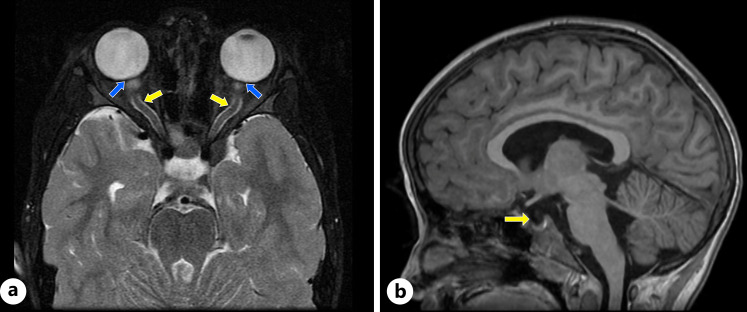

Case presentation: A 6-year-old female presented to our pediatric hospital with binocular horizontal diplopia, headache, fever, malaise, and suspected papilledema 47 days after an embedded tick bite. A diagnosis of Lyme disease had been made 10 days prior in the community based on positive serologies and erythema migrans, but she developed a Jarisch-Herxheimer reaction within 24 h of oral doxycycline, leading to an antibiotic change to amoxicillin. During the hospital admission, an ophthalmological examination revealed papilledema and IH was evidenced by an opening pressure of 36 mm Hg and brain MRI findings. The lumbar puncture revealed pleocytosis and positive cerebrospinal fluid antibodies for Borrelia. The patient was initially treated with 2 days of ceftriaxone, followed by a 12-day outpatient course of doxycycline for LNB. High doses of acetazolamide (500 mg TID) were needed to achieve symptom control. Two months after her hospital discharge, there was resolution of papilledema and the acetazolamide was weaned.